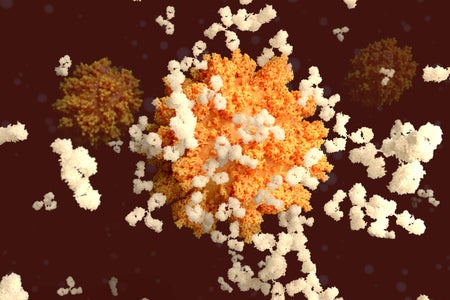

COVID Antibody Treatments Show Promise for Preventing Severe Disease

Uptake by patients and physicians has been low in the U.S. even though some therapies have been authorized for months

Evidence for Convalescent Plasma Coronavirus Treatment Lags behind Excitement

Despite calls for more rigorous clinical trials, the Food and Drug Administration has granted an emergency authorization for the therapy